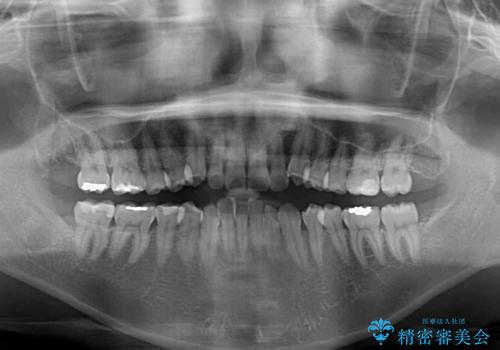

- 前歯の叢生と八重歯を気にして来院された患者様です。

インビザライン単体で改善することも可能ですが、八重歯とその後方にある歯列を確実移動させないと、上下正中がずれてしまう可能性があります。

インビザライン単体での治療ではなく、カリエール・ディスタライザーという補助装置を併用して、より確実性を上げることとしました。

補助装置で八重歯を解消しながら、並行してインビザラインで歯列を整えることとしました。